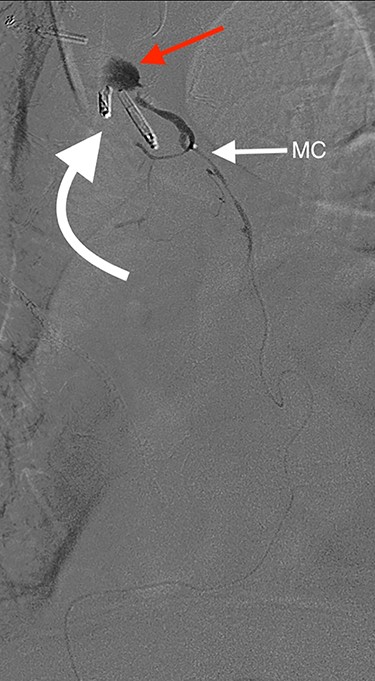

Angiography of the right gastro-epiploic artery. Arrowhead = celiac trunk; Arrow = right gastro-epiploic; Curved arrow = OG anastomosis.

Eight days later, he represented with an upper gastrointestinal bleed with massive haematemesis requiring immediate intubation for airway protection. Computer tomography angiography was unremarkable and an emergency gastroscopy revealed an extensive amount of blood and clot in the oesophagus and gastric conduit (limiting the view), but no active bleeding point. Conservative treatment in the Intensive Care Unit (ICU) with blood transfusion, proton pump inhibitors and life support were implemented. Another large bleed occurred 2 days later and a repeat gastroscopy revealed a non-bleeding visible vessel at the OG anastomosis and a haemostatic clip was applied. However, over the next 10 days, the patient remained blood transfusion dependent and had two further endoscopies. The first was unremarkable, but the second endoscopy re-demonstrated the luminal vessel at the OG anastomosis, with no evidence of the previously placed clip. This was felt to be the cause of his intermittent and problematic bleeding, so another haemostatic clip was attempted, resulting in pulsatile, moderate volume arterial bleeding. The procedure was abandoned and the patient transported immediately to the Interventional Radiology Suite. Right femoral access was obtained and angiography performed. The thoracic aorta was normal, so the celiac trunk was cannulated and angiography of the right gastro-epiploic artery performed (Fig. 1), revealing active extravasation of contrast at the OG anastomosis as shown in Fig. 2. A microcatheter was advanced along the length of the right gastro-epiploic artery to the OG anastomosis and coil embolization was performed (Fig. 3). Care had to be taken to ensure that the embolization was as distal as possible to limit the risk of ischaemic complications. The patient required lengthy ongoing care in the ICU for organ dysfunction but remained hemodynamically stable after embolization without evidence of conduit ischaemia. His hospital stay was obviously lengthy, but he was ultimately transferred to a rehabilitation unit.